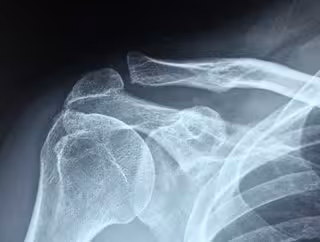

Descubren nuevas estructuras en el manguito rotador que inspirarán nuevas técnicas de reparación

Archivo - Manguito rotador

Investigadores de la Universidad de Washington y la Universidad de Columbia, en Estados Unidos, han descubierto, mediante una novedosa técnica de imagen, una arquitectura fibrosa hasta ahora desconocida entre los tendones del manguito rotador y sus anclajes óseos en el hombro, que puede dar lugar a nuevas técnicas de reparación de lesiones, según publican en la revista 'Science Advances'.

Los desgarros del manguito de los rotadores, una de las lesiones tendinosas más comunes en los adultos, se producen cuando los tendones se desprenden o se rompen cerca del hueso. El 30% de los adultos mayores de 60 años sufren un desgarro, y más del 60% de los adultos mayores de 80 años tienen un desgarro.

Para observar más de cerca la entesis, o el material de transición donde cada uno de los cuatro tendones del manguito rotador se une al hueso, el equipo aplicó una novedosa técnica de microtomografía computarizada (microCT).

Las imágenes revelaron un lugar oculto en la entesis del tendón del supraespinoso de los hombros de los ratones, donde las fibras del tendón se insertan directamente en el hueso en un 30% de la conocida huella de fijación.